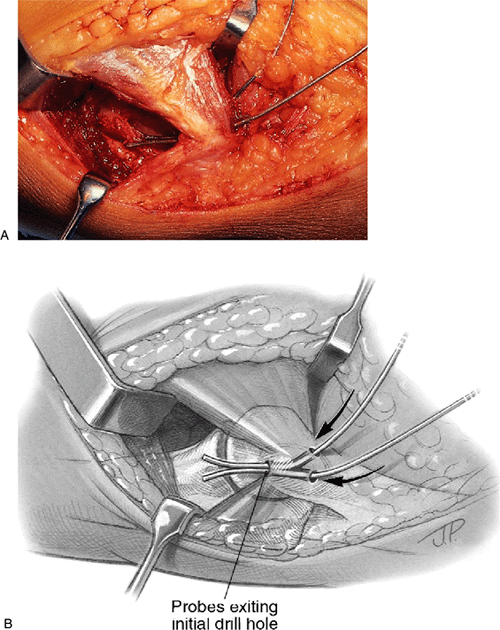

epicondyle, creating bone tunnels though which the graft will be

epicondyle. The drill holes diverge and exit separately in the cubital

tunnel posteriorly (Fig. 14-13).

located at the level of the tubercle on the medial aspect of the

coronoid process. These holes are separated by approximately 1 cm (Fig. 14-13).

![]() |

Figure 14-12. A,B: